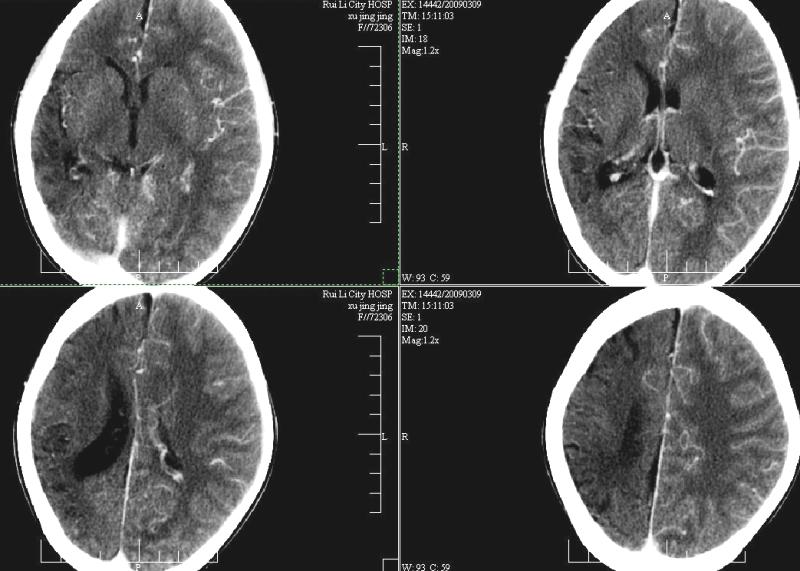

标题: PED1810:F,9岁。头痛,昏倒,一周一次,共半年。 [打印本页]

标题: PED1810:F,9岁。头痛,昏倒,一周一次,共半年。

ct:右顶叶脑软化灶合并右侧大脑半球发育不良可能。

右侧大脑半球脑萎缩。

支持楼主!右侧强化明显较左侧低.可能血管引起的吧.

支持楼主!右侧强化明显较左侧低.可能由血管发育不良引起的吧.

支持大脑发育不全----右侧大脑中动脉较对侧细小。建议cta 或mra 检查